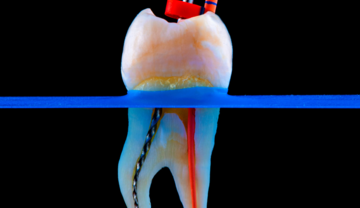

O que é?

Especialidade responsável por tratar inflamações ou infecções dentro do dente (“nervo”). Com tecnologia moderna, o tratamento torna-se rápido, seguro e confortável.

Como funciona:

- Anestesia local

- Remoção da infecção

- Limpeza e modelagem dos canais

- Selamento tridimensional

- Restauração final do dente

Indicado para:

- Dor intensa

- Cáries profundas

- Sensibilidade prolongada

- Traumas e fraturas

- Infecções (abscesso)

- Procedimentos minimamente invasivos

Benefícios:

- Acaba com a dor

- Salva o dente natural

- Evita extrações

- Recupera função e estética